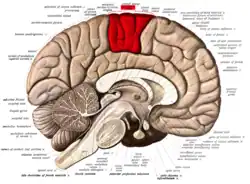

![]() Medial surface of left cerebral hemisphere. (Paracentral lobule is shown in red.) | |

In neuroanatomy, the paracentral lobule is on the medial surface of the cerebral hemisphere and is the continuation of the precentral and postcentral gyri. The paracentral lobule controls motor and sensory innervations of the contralateral lower extremity. It is also responsible for control of defecation and urination.

It includes portions of the frontal and parietal lobes:[1]

- The anterior portion of the paracentral lobule is part of the frontal lobe and contains a little portion of Brodmann's area 6 (SMA): this is because the paracentral sulcus (branch of the cingulate sulcus) does not correspond to the precentral sulcus on the medial plane.

- The posterior portion is considered part of the parietal lobe and deals with somatosensory of the distal limbs.

While the boundary between the lobes, the central sulcus, is easy to locate on the lateral surface of the cerebral hemispheres, this boundary is often discerned in a cytoarchetectonic manner in cases where the central sulcus is not visible on the medial surface.